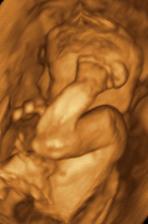

♥ dne 18.9. 3D UTZ - s manželem jsme si móóóc užívali, mrňousek je úúúžasný, takový skříteček..., ale náš 🙂